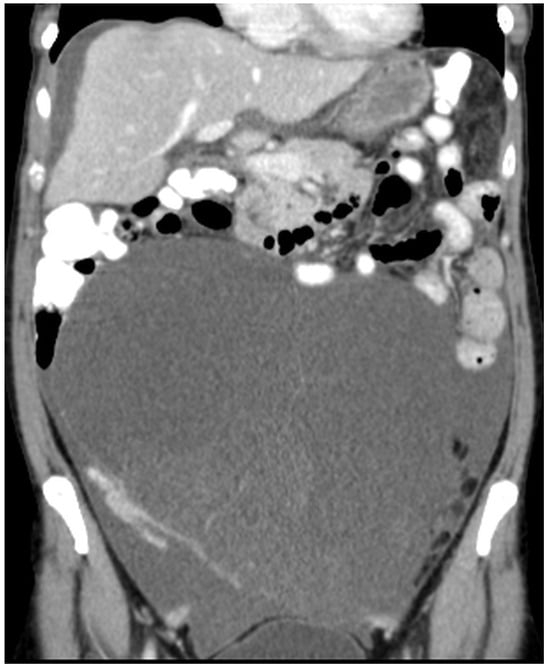

Figure 12. CT, venous phase, coronar plane.

Figure 11, Figure 12, Figure 13, Figure 14 and Figure 15. Advanced stage of the disease. The abdomen is full of tumors and mucin. Typical signs are heterogeneous or hypodense masses in the form of lobules often with septa, which could be enhanced by contrast and could be associated with calcifications.

Patients with a misdiagnosed rupture of the mucocele may develop pseudomyxoma peritonei. It is characterized by the presence of an abundant gelatinous substance in the abdomen. Diffuse, progressive, and abundant mucin-containing tumor cells are typical of this disease [2] (Figure 11, Figure 12, Figure 13, Figure 14, Figure 15 and Figure 16). The interval between rupture and advanced disease is several years. In our clinical series, the interval was about 5 years. In the literature, we found a wide range of this interval from 12 months to 10 years [9,10]. The natural history of PMP revolves around the “redistribution phenomenon”, whereby mucinous tumor cells accumulate in the Douglas pouch, in the diaphragm (more on the right), and the small and large omentum (Figure 17). The small intestine is less involved [4]. Pseudomyxoma peritonei is a slowly progressing disease, which fills the peritoneal cavity over time. There are several classifications of pseudomyxoma. The most commonly used is the PSOGI classification [2]. Mucinous accumulation progresses to malnutrition, bowel obstruction, and respiratory compromise. Rarely, the tumor may spread to the pleural cavity. This has been described in 5.4% of cases. It may occur spontaneously or as a result of diaphragmatic injury during cytoreduction [8,11].